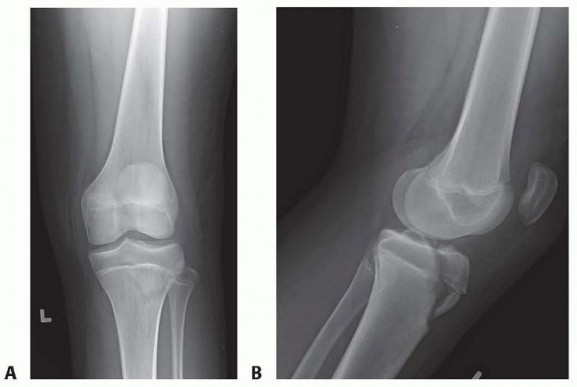

Chapter 34 Tibial Tuberosity Fractures Eric W. Edmonds DEFINITION Tibial tuberosity fractures are rare fractu…